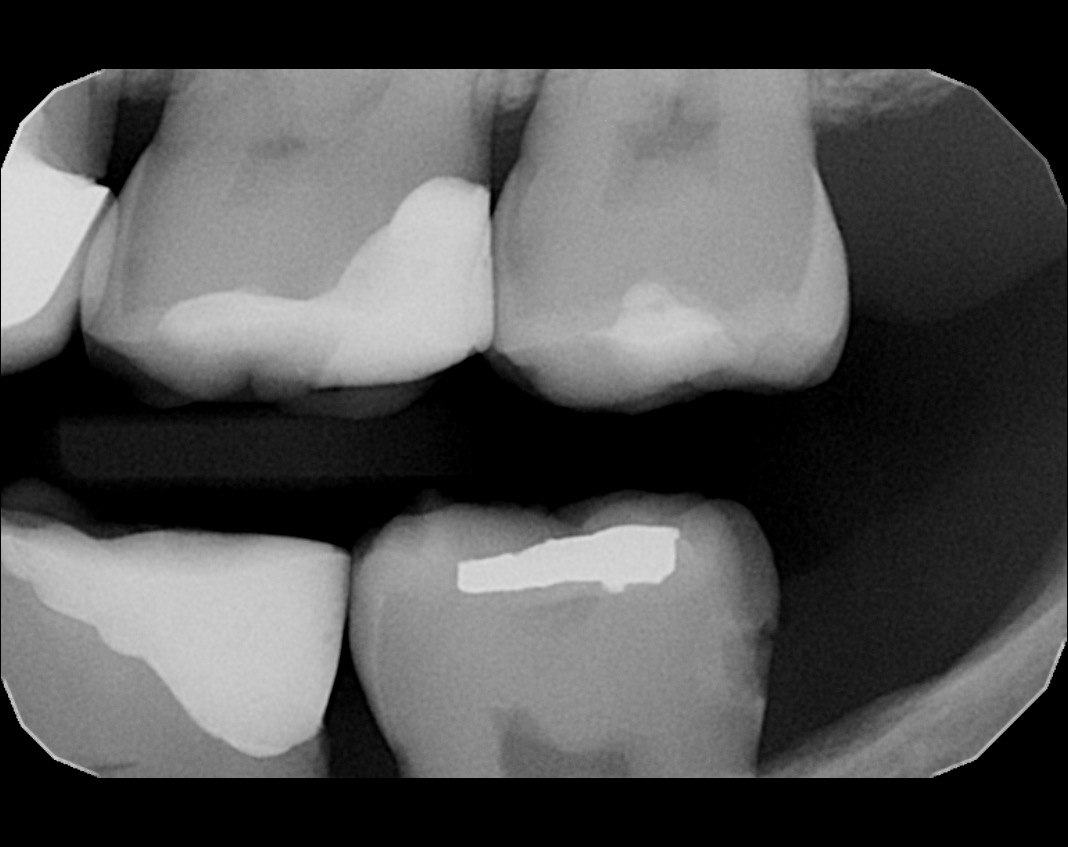

Question 1: What materials cannot be seen in the print of the X ray?

Question2: Which surface shows overhang?

Question 3: Which option is not evident on the print of the X ray?

Question 4: Which options cannot be seen in the print of the X ray?

Question 5: What options cannot be selected for tooth # 4.6?

Question 6: What options cannot be seen in the print of the X ray?

Question 7: What option cannot be identified on the print of the X ray?

Question 8: What condition can be seen in the X ray?

Question 9: Which option cannot be seen in the lower jaw?

Question 10: Which option can be selected for the following X ray?